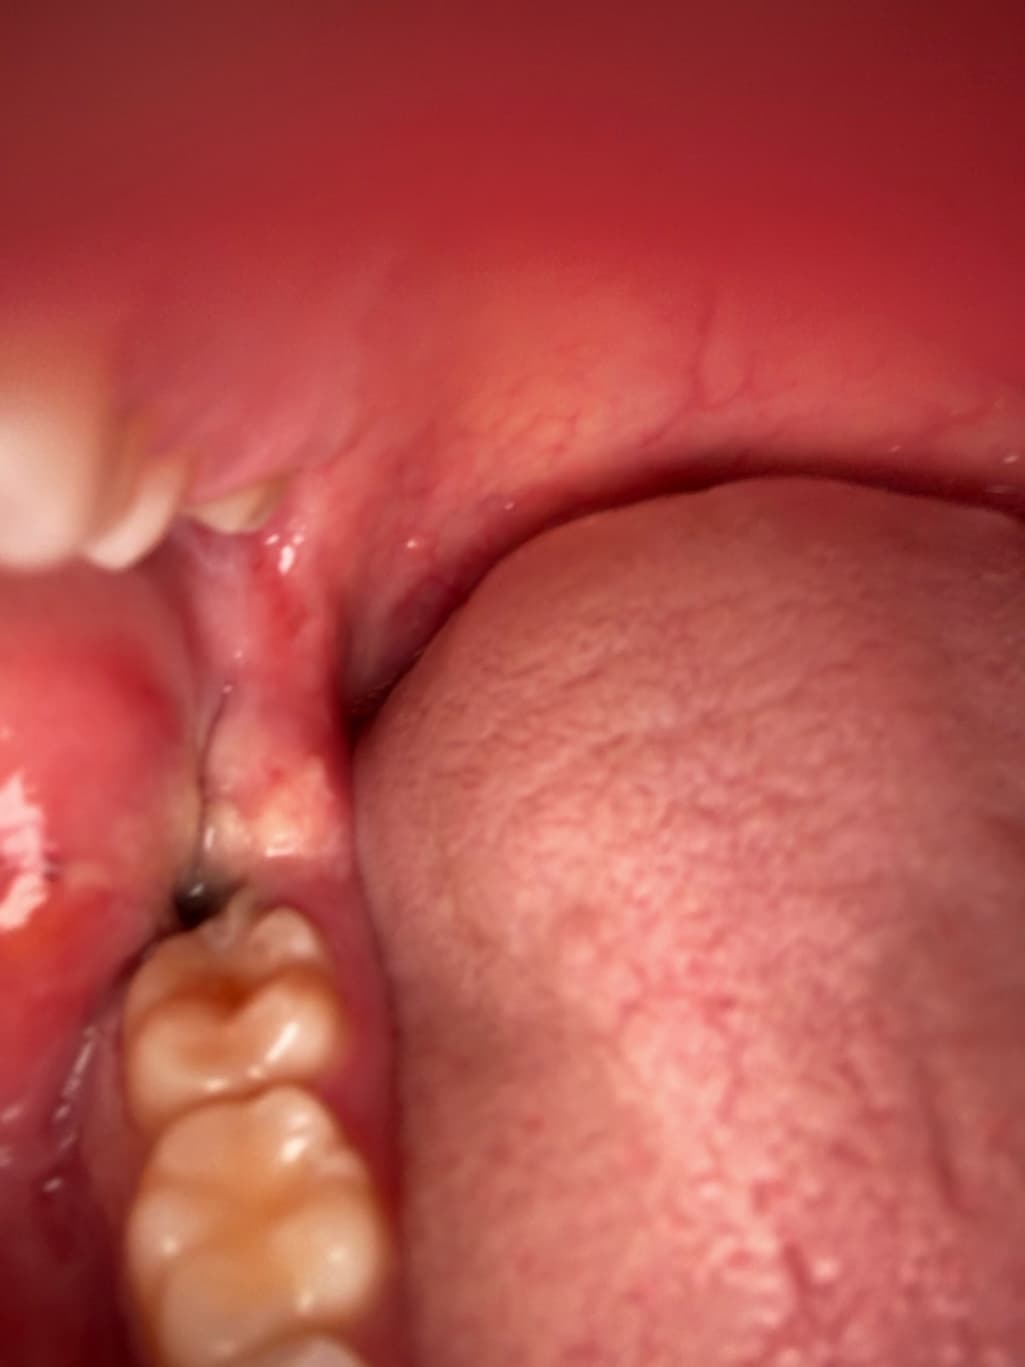

수요일날 발치를 했는데요 원래 피떡이 있던 자리에 지금보니 저렇게 크기도 훨씬작아지고 색깔이 거의 검정색에서 회색으로 보이게 변했어요 특히 크기가 엄청작아지고 주변에 하얀색으로 덮혔습니다 드라이소켓이 구취나고 회색으로 변한다던데 혹시 드라이소켓일 가능성이 있나요??ㅠㅠ

드라이소켓은 통증이 극심하기 때문에 아닐 것이며 사진상으로도 특별히 문제는 보이지 않습니다.

지금으로선 특별히 치유에 문제가 있어 보이진 않습니다 발치 후 주의사항 잘 지키시면 됩니다